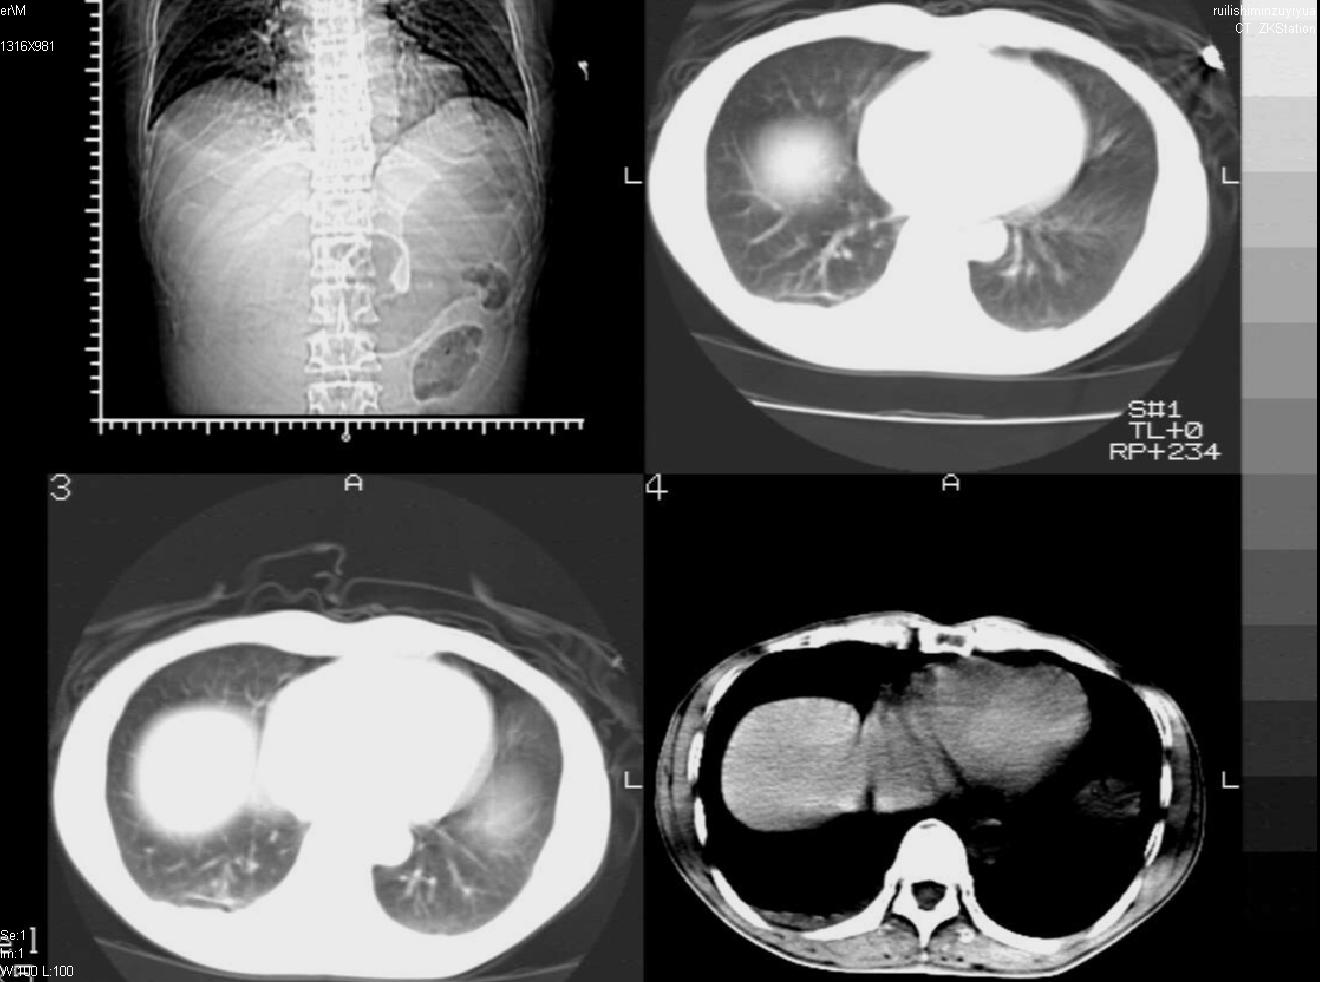

以下是引用liuyue在2007-12-3 6:27:00的发言:[br]右肾区可见密度不均匀、边缘欠清之肿块影,肾脏筋膜增厚,周围脂肪密度增高。右侧胸膜腔内可见少量液体密度影。考虑:1.右肾错构瘤(肾血管平滑肌脂肪瘤)可能性大。2.右侧少量胸腔积液。[br] 鉴别:1.肾脂肪肉瘤。2.肾平滑肌肉瘤。3.肾错构瘤恶变。